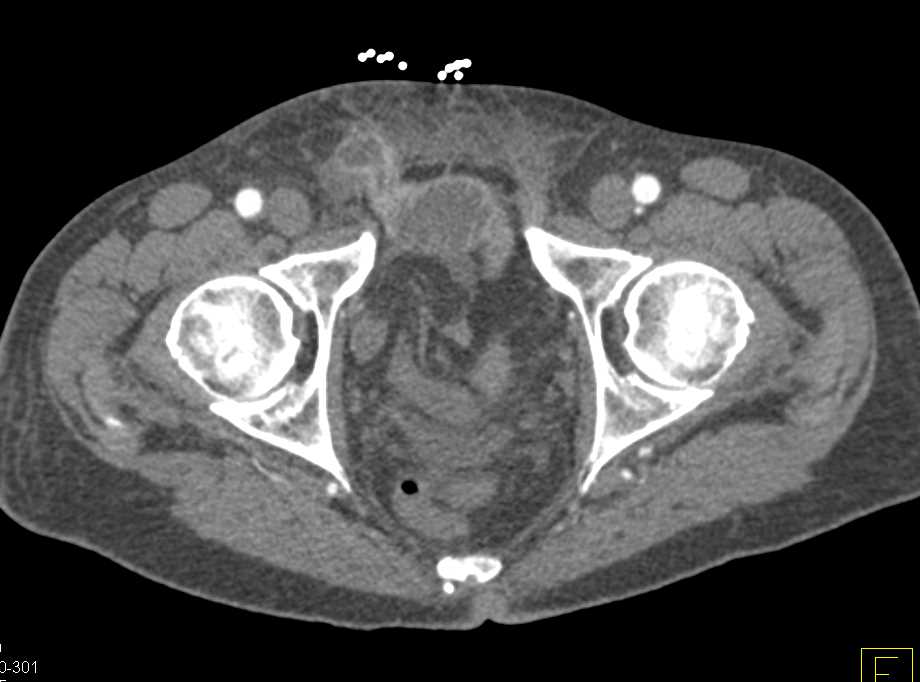

Ct Scan Of Inguinal Hernia. They review and label key anatomic structures, present cases Appearance of bowel loops within the lesion;

The doctor explained that her distrust of radiologists was based on a study that showed that a majority of ct and mri scans do not accurately diagnose hernias. The radiologic femoral triangle is particularly well visualized on coronal reconstructions, which should lead to accurate diagnosis of femoral hernias from coronal images. Preoperative ct (a) shows peritoneal fluid (asterisk) in the hernia sac, herniation of the ipsilateral aspect of the urinary bladder (arrow) in the inguinal canal.

No acute inflammatory process.the nurse told me that means i do not have a hernia. More important, ct findings can be used to diagnose unsuspected hernias and to distinguish hernias from masses of the abdominal wall, such as tumors, hematomas, abscesses, undescended testes, and aneurysms. Abdominal ct of inguinal hernia is indicated in unspecific abdominal symptoms, in.

Extra essential, ct findings can be used to diagnose unsuspected hernias and to differentiate hernias from plenty of the stomach wall, akin to tumors, hematomas, abscesses, undescended testes, and aneurysms. A physical exam is usually all that's needed to diagnose an inguinal hernia. Dumanian suspects a hernia but cannot confirm it based on a physical examination alone, he may recommend an imaging test.

Intraperitoneal Organs Into The Inguinal Canal Or Scrotum Is Visible On Computed Tomography (Ct) Scans. Direct Inguinal Hernia Involves Direct Prolapse Of Intraperitoneal Organs Fi”Om Inside The Inferior Epigastric Artery, Without Passing Through The Inguinal Canal.